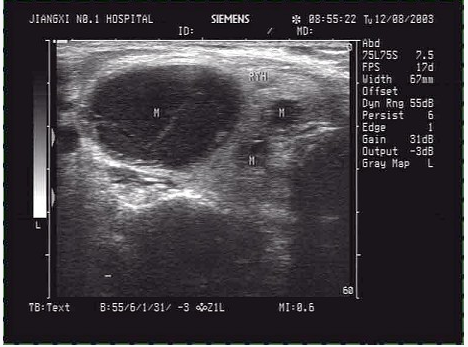

临床资料:男,50岁,自述胃癌术后3年余。超声综合描述:右锁骨上窝扫查可见数个长圆形低回声区,最大1.7cm×1.1cm,边界尚清,内回声欠均匀,部分互相融合,CDFI:内可见少许动脉血流信号。见下图及彩图。

超声提示()。

A.右锁骨上窝淋巴结结核

B.右锁骨上窝囊肿

C.右锁骨上窝肿大淋巴结(淋巴结转移瘤)

D.右锁骨上窝正常淋巴结声像图